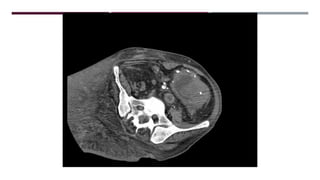

MASA SÓLIDO/QUISTICA

MESENTERIO/PERITONEO

LESION FOCAL PARED

ABDOMINAL

CALCIFICACION ESPLÉNICA